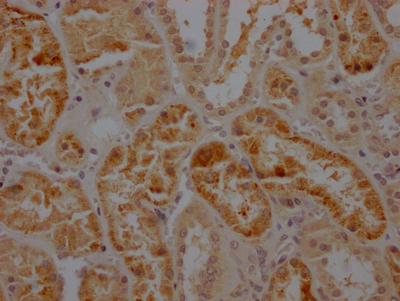

IHC image of CSB-RA782200A0HU diluted at 1:100 and staining in paraffin-embedded human kidney tissue performed on a Leica BondTM system. After dewaxing and hydration, antigen retrieval was mediated by high pressure in a citrate buffer (pH 6.0). Section was blocked with 10% normal goat serum 30min at RT. Then primary antibody (1% BSA) was incubated at 4℃ overnight. The primary is detected by a Goat anti-rabbit IgG polymer labeled by HRP and visualized using 0.05% DAB.